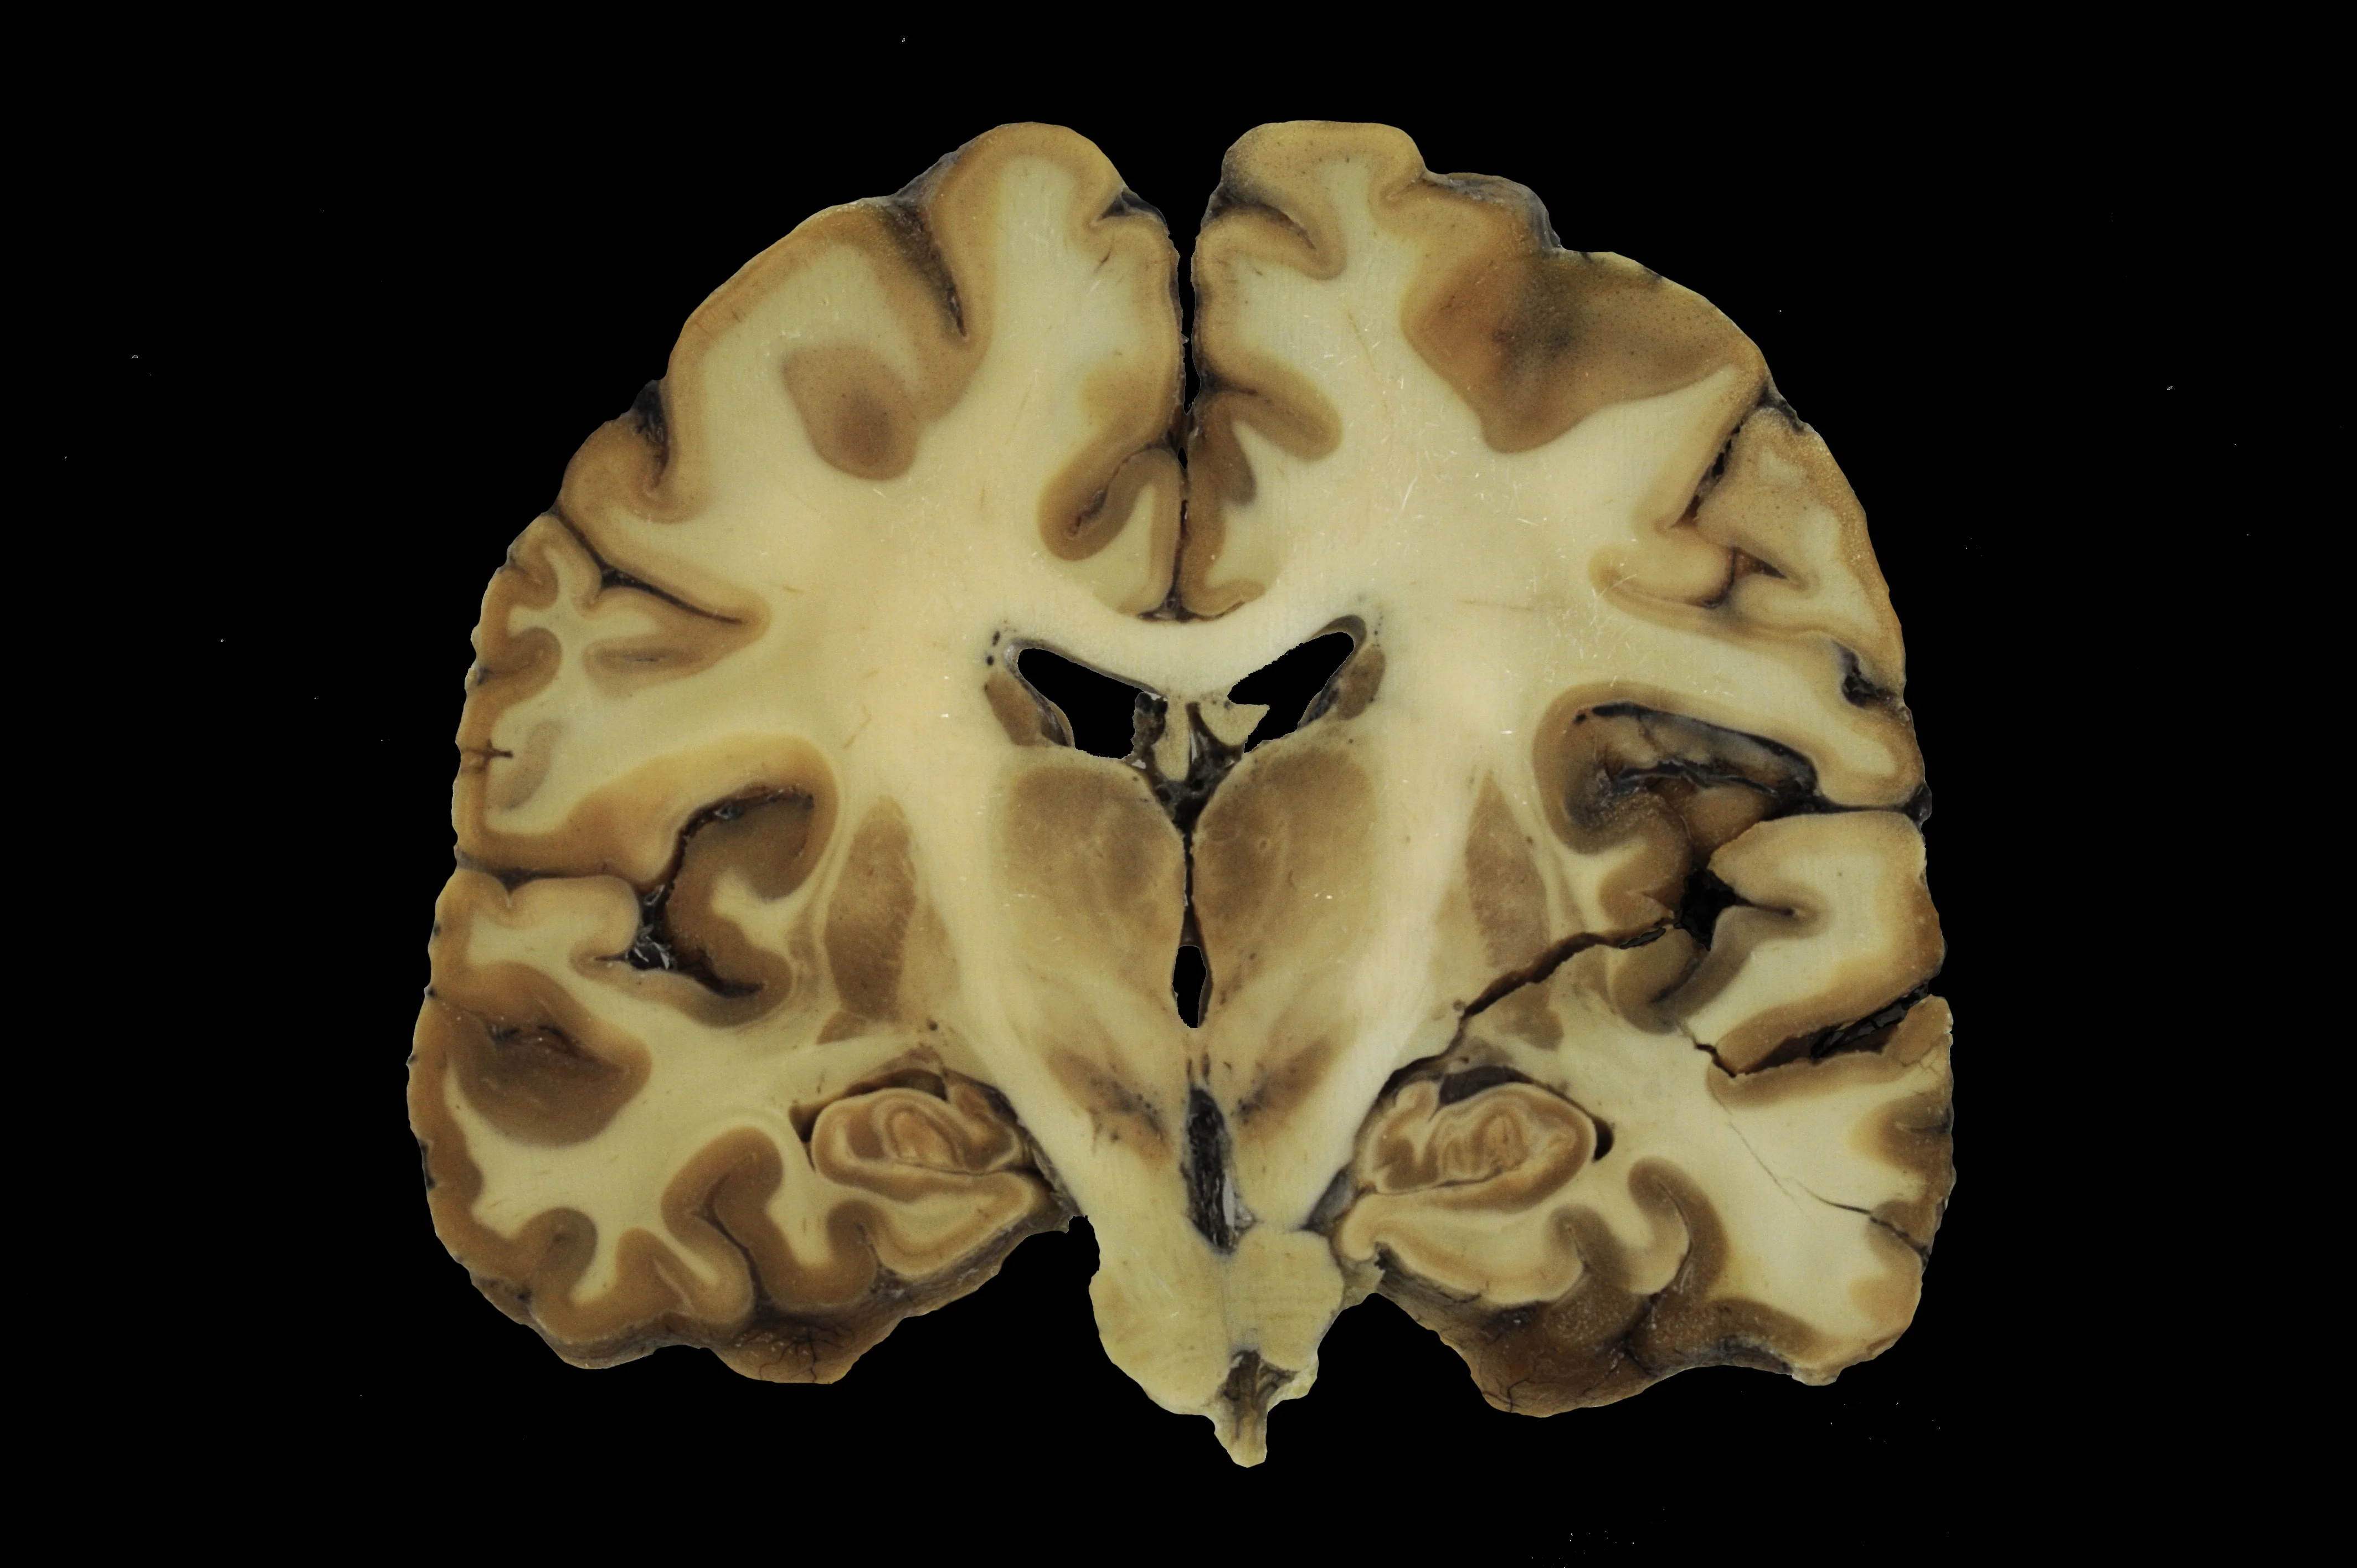

Durch anschließende weitere Differenzierung der Anlagen des Prosencephalons in zwei Hirnbereiche sowie die Untergliederung des Rhombencephalons in zwei Bereiche durch die Brückenbeuge (Flexura pontina) wird dann die für alle Wirbeltiere typische fünfteilige Gliederung des Gehirns erreicht, angelegt als fünf sekundäre Hirnbläschen:

- Telencephalon (Endhirn),

- Diencephalon (Zwischenhirn),

- Mesencephalon (Mittelhirn),

- Metencephalon (Hinterhirn) und

- Myelencephalon (Markhirn).

Aus dem Lumen des Neuralrohrs wird das liquorführende System der Hirnventrikel und der Zentralkanal des Rückenmarks.